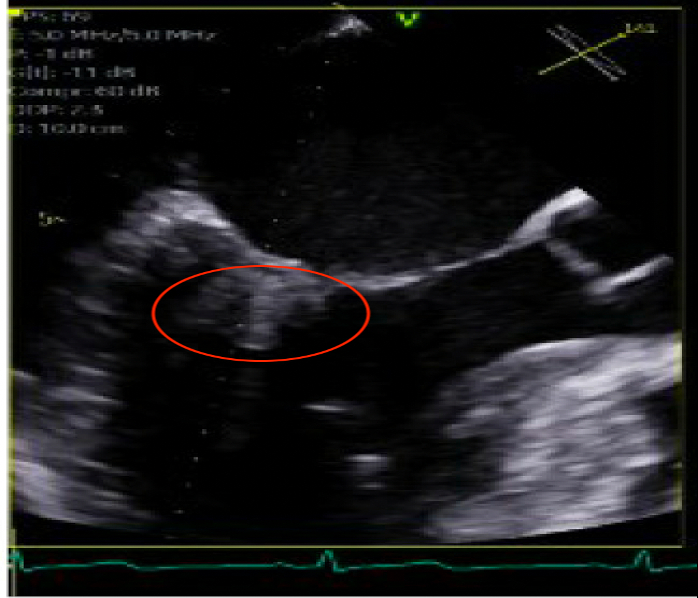

A 33-year-old woman with sickle cell disease (HbSS) presented with vaso-occlusive crisis, persistent fever, and a new cardiac murmur suggestive of mitral regurgitation. Initial transthoracic echocardiography revealed a mobile, vegetation-like mass (0.9×1.5 cm) on the posterior mitral leaflet (Figure 1). Blood cultures transiently yielded Escherichia coli, prompting treatment with antibiotics for suspected infective endocarditis. Despite antibiotic treatment, the patient continued to have febrile episodes and labs were notable for significant eosinophilia (>1500/µL), raising suspicion for a non-infectious etiology such as Loeffler endocarditis.

Transesophageal echocardiography demonstrated an extensive lesion (1.4×1.3 cm) contiguous with the subvalvular myocardium, consistent with mural involvement and fibrotic changes atypical for bacterial endocarditis but highly suggestive of eosinophilic endocarditis (Figures 2-3). Comprehensive hematologic evaluation identified elevated serum IgE, tryptase levels, and confirmed the presence of the FIP1L1-PDGFRA fusion gene, supporting a diagnosis of myeloproliferative HES.